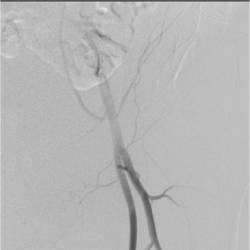

Physician Assistant Lower Limb and Thorax Written Examination - Radiology Pool

Gallery of Unlabled Radiographs from Lecture (Dr. French) - 2020

Click a thumbnail to enter the gallery display. Click the file name link at the bottom left of the gallery display to view the image at high resolution.